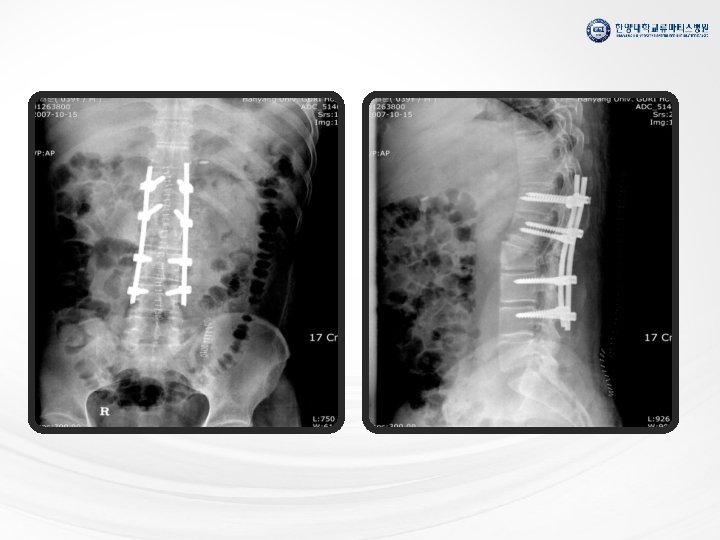

척추 관절염 방사선학적 단계 비방사선학적 단계 Modified New York Criteria 1984 요통 요통 MRI

척추 관절염 방사선학적 단계 비방사선학적 단계 Modified New York Criteria 1984 요통 요통 MRI 상에 천장골염 방사선학적 천장골염 Rudwaleit M et al. Arthritis Rheum 2005; 52: 1000 -8 (with permission) 요통 Syndesmophytes